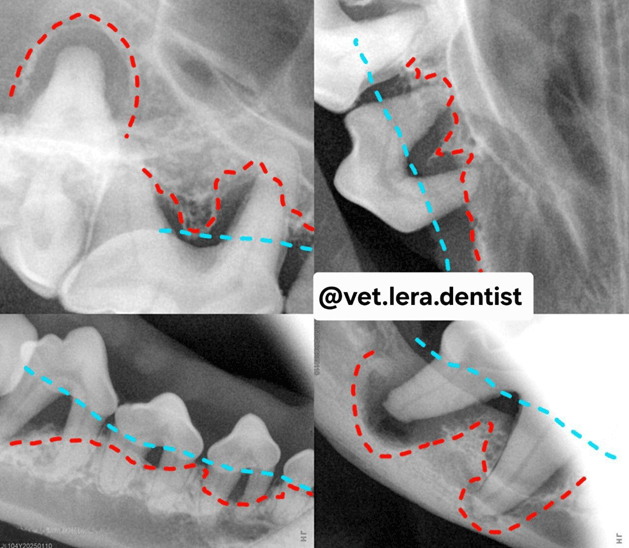

1-4-25092025.png

Фото 4. Дентальный рентген. Пудель. Гнойным пародонтит.

Красная линия — фактическая потеря костной структуры, абсцессы в области корней

Голубая линия — как должно быть в норме.